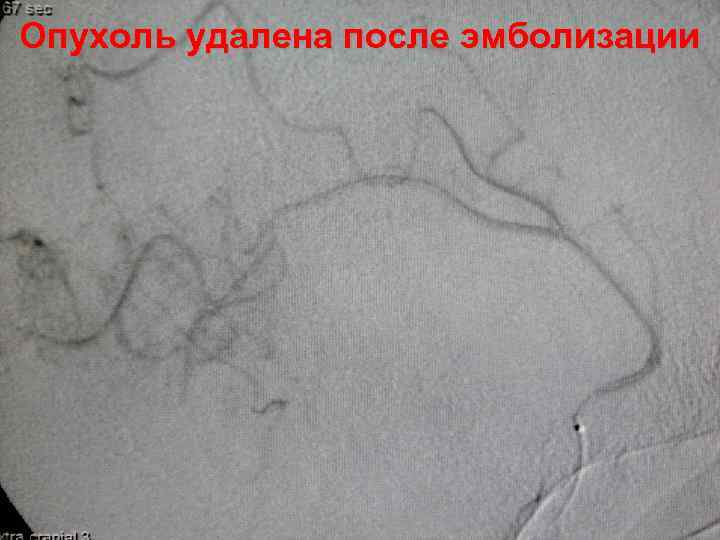

Опухоль удалена после эмболизации 59